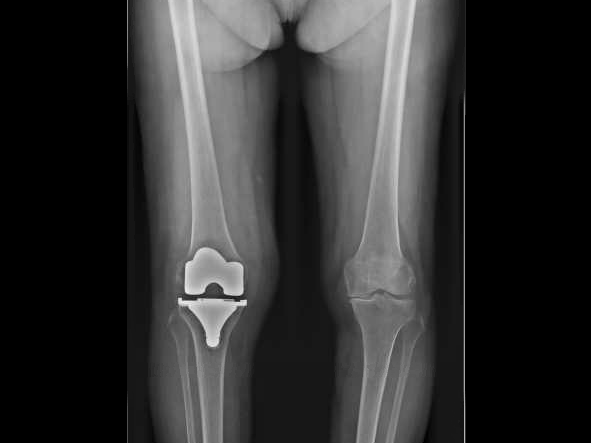

Album photo